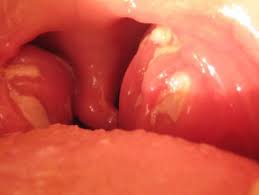

Based on the severity of the symptoms, a healthcare provider may recommend treatment of specific organ systems affected by infectious mononucleosis. See full list on mayoclinic.org Signs and symptoms of mononucleosis may include: You can help protect yourself by not kissing or sharing drinks, food, or personal items, like toothbrushes, with people who have ebv infection. This virus is spread through saliva, and you may catch it from kissing or from sharing food or drinks.

You can also develop airway difficulties from enlarged tonsils.

This virus is spread through saliva, and you may catch it from kissing or from sharing food or drinks. More images for mononucleosis syndrome » See full list on my.clevelandclinic.org There is no specific treatment for ebv. Because your spleen may become enlarged as a result of infectious mononucleosis, you should avoid contact sports until you fully recover. Cmv mononucleosis is estimated to comprise 7% of all infectious mononucleosis syndromes. Ebv infections in children usually do not cause symptoms, or the symptoms are not distinguishable from other mild, brief childhood illnesses. However, some people may feel fatigued for several weeks or even months. Infectious mononucleosis mainly affects younger adults. Rash many people become infected with ebv in childhood. More white blood cells (lymphocytes) than normal 2. You can help protect yourself by not kissing or sharing drinks, food, or personal items, like toothbrushes, with people who have infectious mononucleosis. You can get it through kissing, but you can also be exposed by sharing a.